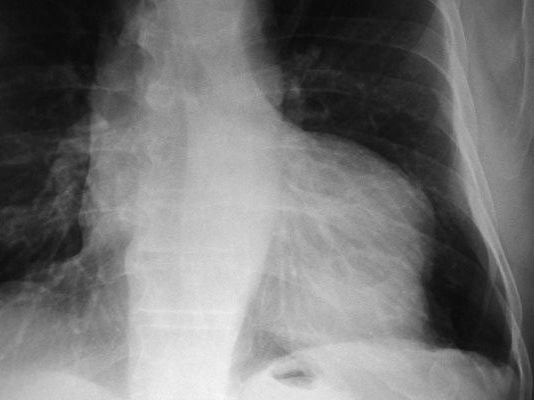

Neumonia basal derecha.

Neumonía basal derecha.